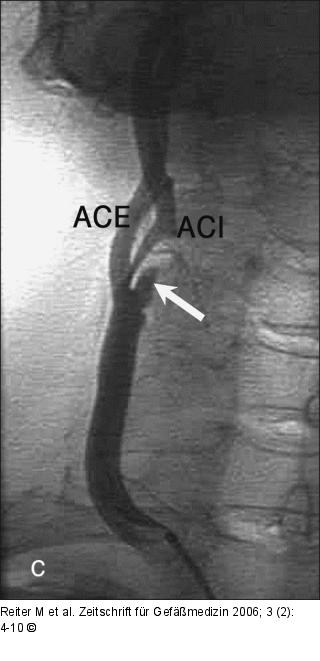

Abbildung 2a-c: B-Flow - Plaque Tief ulzerierte Plaque mittels B-Flow- (a), Farbdoppler (b) und i. a. DSA (c). (Z) zeigt das Ulkus. |

Abbildung 2a-c: B-Flow - Plaque

Tief ulzerierte Plaque mittels B-Flow- (a), Farbdoppler (b) und i. a. DSA (c). (Z) zeigt das Ulkus. |